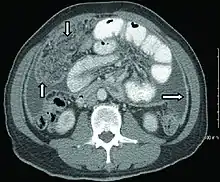

Abdominal infections include gastrointestinal tuberculosis (which is important to distinguish from Crohn's disease, since immunosuppressive therapy used for the latter can lead to dissemination), tuberculous peritonitis, and genitourinary tuberculosis.[4]